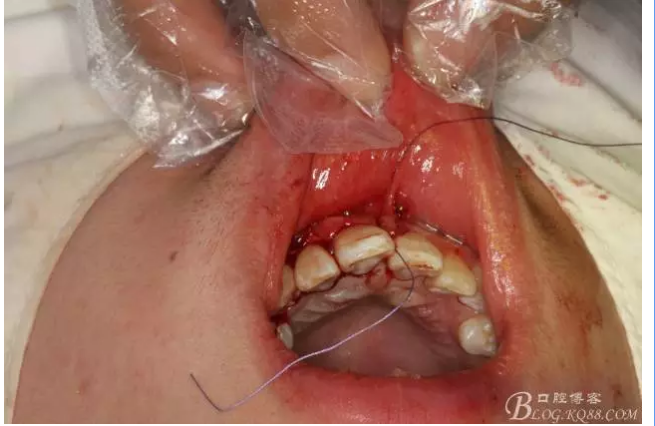

圖11.MTA倒充填預(yù)備好的根尖3mm。

圖12.倒充填完畢的12根尖區(qū)影像

圖13.巨大骨腔填塞膠原蛋白海綿。

圖14.縫合水平切口